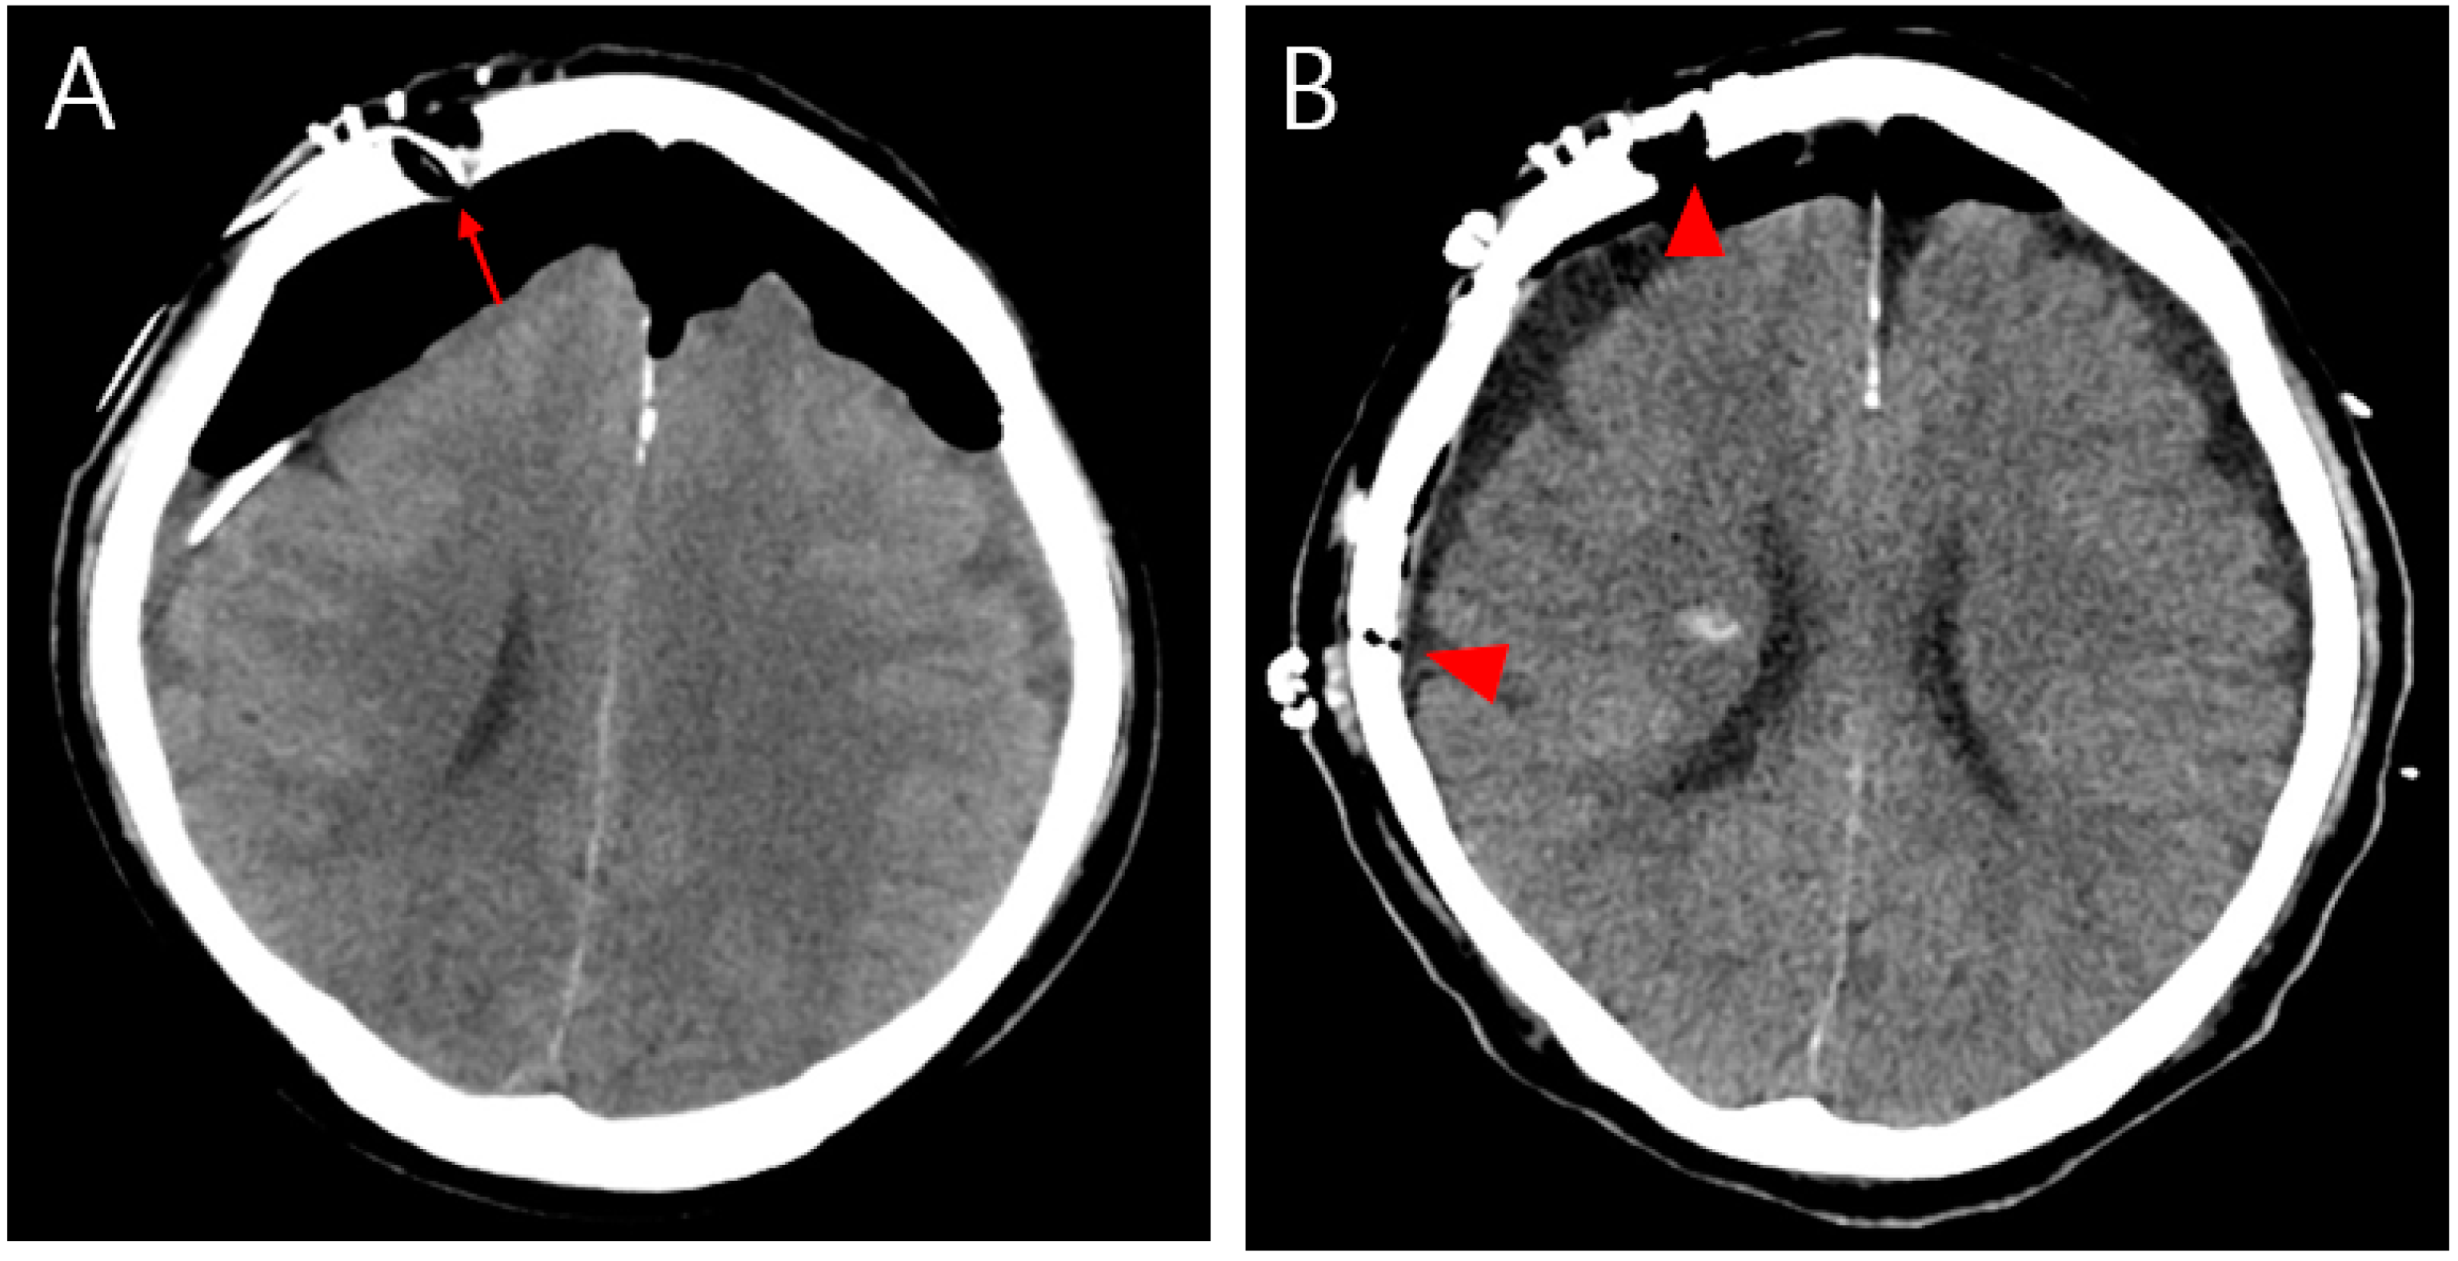

(A) Postoperative brain CT showing persistent intracranial air that compressed the brain parenchyma after burr hole trephination on the right frontal area (arrow). (B) After craniotomy, the CT image of the brain showed an improvement in pneumocephalus upon a reduction in the intracranial air (arrowhead).